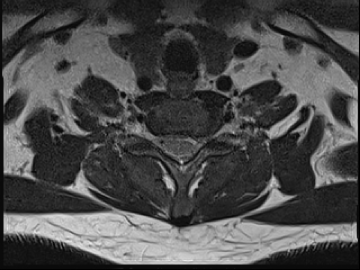

질환을 의심해 볼 수 있는 자가진단법으로 정확한 진단은 MRI와 같은 영상학적 검사를 필요로 합니다.

목디스크 수술 치료

2019.05.25

2022.09.13

2022.11.10

2022.11.16